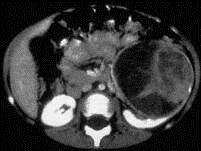

问题 女,54岁,发现腹部包块,请根据所示图像,选择最可能诊断 ( )

选项 A、左侧囊性肾癌 B、左侧肾血管平滑肌脂肪瘤 C、左侧单纯性肾囊肿 D、左侧肾囊肿合并出血 E、左侧肾癌

答案 A